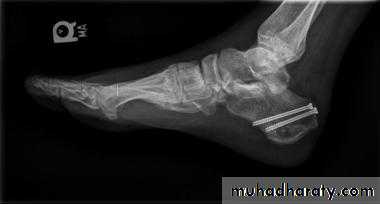

Calcaneal fracture, also known Don Juan fracture, is a fracture of the calcaneus. It is usually caused by a fall from height when one lands on their feet. These fractures represent approximately 2% of all fractures but 60% of tarsal bone fractures.